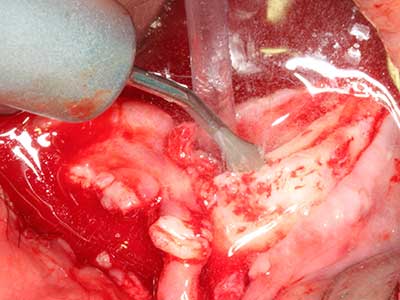

Sollen chirurgische Eingriffe mit unmittelbarer Knochenbeziehung an empfindlichen Strukturen wie Blutgefäßen oder Nerven erfolgen, so bergen rotierende Instrumente ein erhebliches Potential an iatrogener Schädigung. Gerade bei Nervdarstellungen nach iatrogener Schädigung, oder aber im Zuge einer Nervlateralisation für resektive und rekonstruktive Eingriffe oder Implantatinsertionen können piezoelektronische Geräte hilfreich sein Knochendeckel zu präparieren und nervnahe Hartgewebsanteile zu entfernen (Abb. 17-20). Ein leichter Kontakt des Nervstrangs zur Piezospitze bleibt dabei in der Regel folgenlos – allerdings kann eine unvorsichtige Vorgehensweise mit sägeartigen Bewegungen bzw. Ansätzen bei noch vorhandener knöcherner Unterlage durchaus temporäre oder aber auch permanente Nervschädigungen verursachen. Das Risiko einer solchen Schädigung wird jedoch als wesentliche geringer eingeschätzt als unter Anwendung von Säge- oder Fräsinstrumenten (Pereira, Gealh et al. 2014).

Indikation: Wurzelspitzenresektion

Indikation: Nervnahe Präparation